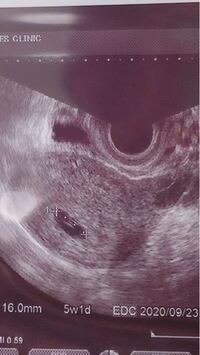

5w3d 胎嚢 小さい 妊娠5週目 5w4d に 内診検査にて ついに胎嚢が確認 5週の胎嚢サイズの平均は16